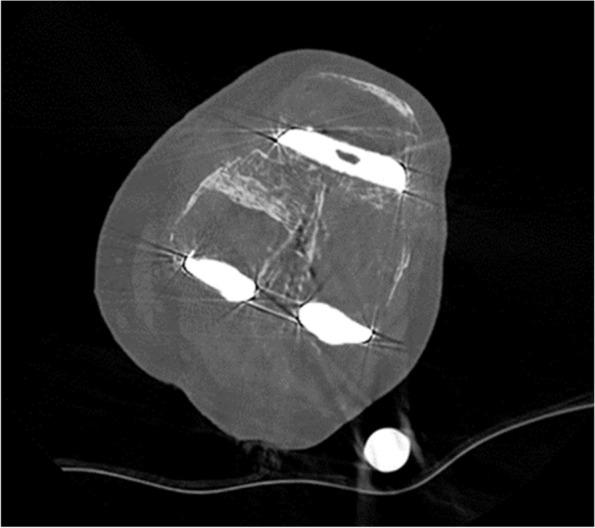

机器人辅助翻修全膝关节置换术:一种新型手术技术。

Robotic-assisted revision total knee arthroplasty: a novel surgical technique.

Revision total knee arthroplasty is a challenging procedure. The robotic-assisted system has been shown to enhance the accuracy of preoperative planning and improve reproducibility in primary arthroplasty surgeries. The aim of this paper was to describe the surgical technique for robotic-assisted revision total knee arthroplasty and the potential benefits of this technique.

This single-centre retrospective study included a total of 19 patients recruited from April 1, 2021 to April 30, 2022. Inclusion criteria were patients who had Mako™ robotic-assisted revision total knee arthroplasty done within the study period with a more than 6 months follow-up. Statistical analysis was done using Microsoft Excel 16.0.

All 19 patients were followed up for 6 to 18 months. All patients in this study had uneventful recoveries without needing any re-revision surgery when reviewed to date.

With the development of dedicated revision total knee software, robot-assisted revision TKA can be a promising technique that may improve surgical outcomes by increasing the accuracy of implant placement, and soft tissue protection and achieving a better well-balanced knee.